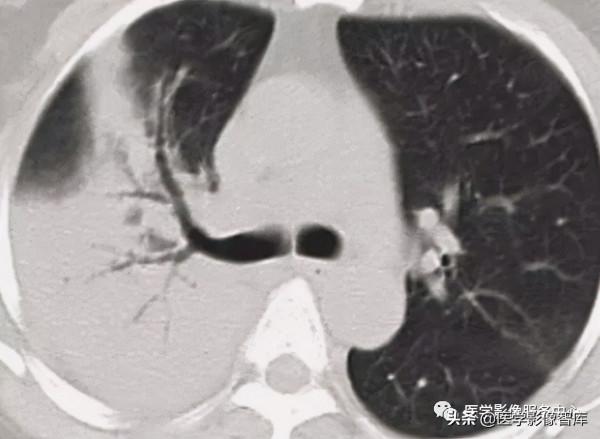

圖19. 陽性⽀⽓管徵 A和B均可⻅⽀⽓管⽓道通向腫塊,⽀⽓管鏡活檢為⾮⼩細胞肺癌

陽性⽀⽓管徵:胸部CT表現為直接通向周圍肺結節或腫塊的⽀⽓管⽓道(圖19A, 19B)。 這是預測經⽀⽓管肺活檢和⽀⽓管內超聲刷洗是否成功的有⼒線索。Gaeta等⼈報道,第四級⽀⽓管⽔平以上發現陽性⽀⽓管徵時,經⽀⽓管活檢和刷洗的成功率為90%。